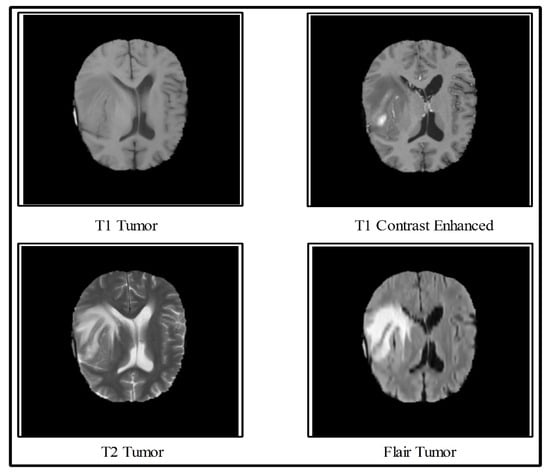

1.1. Significant Challenges and Motivation

- Three datasets such as BRATS 2015, BRATS 2017, and BRATS 2018 were used for the experiments and the statistical analysis to examine the scalability of the proposed classification scheme.